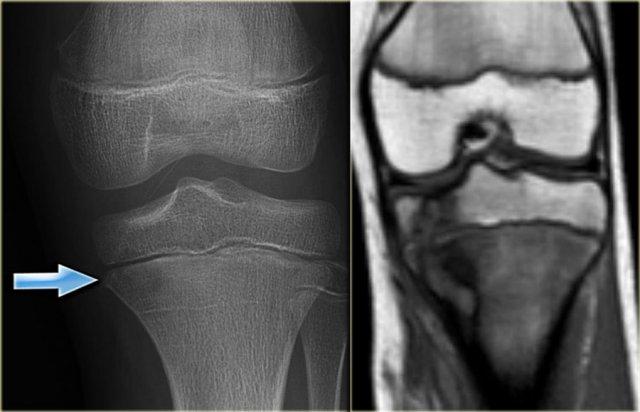

Bên trái là hình ảnh viêm tủy xương thể bán cấp.

Có thể thấy một tổn thương lệch tâm, ranh giới không rõ ở cả hai phía của đĩa sụn tăng trưởng tại đầu trên xương chày.

Hình ảnh này gợi ý mạnh mẽ cho chẩn đoán viêm tủy xương.

Nhìn chung, các tổn thương khác không vượt qua đĩa tăng trưởng.

Bên phải, hình ảnh MRI chuỗi xung T1 mặt phẳng coronal cho thấy một tổn thương vùng hành-đầu xương có ranh giới rõ.

Có vùng ngoại vi tín hiệu thấp do xơ cứng phản ứng, cùng với phù nề lan rộng biểu hiện tín hiệu thấp ở vùng hành xương.

Bên trái là tổn thương tiêu xương không rõ ranh giới ở vùng hành xương đầu gần xương chày với xơ cứng phản ứng lan rộng và phản ứng màng xương dạng đặc.